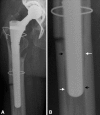

Background: The transfemoral approach is an extensile surgical approach that is performed routinely to facilitate cement and implant removal and improve exposure for revision stem implantation. Previous studies have looked at clinical results of small patient groups. The factors associated with fixation failure of cementless revision stems when using this approach have not been examined.

Results: The average Harris hip score improved from 45.2 (± 14.02) preoperatively to 83.4 (± 11.86) at final followup. Complete radiographic bony consolidation of the osteotomy site was observed in 95% of patients. Dislocations occurred in 9% of patients. Four revision stem fixation failures were observed, all occurring in patients with primary three-point fixation. Three-point fixation was associated with short osteotomy flaps and long revision stems.

Conclusions: The transfemoral approach is associated with a high rate of osteotomy flap bony healing and good clinical results. When using the transfemoral approach, a long osteotomy flap should be performed and the shortest possible revision stem should be implanted.